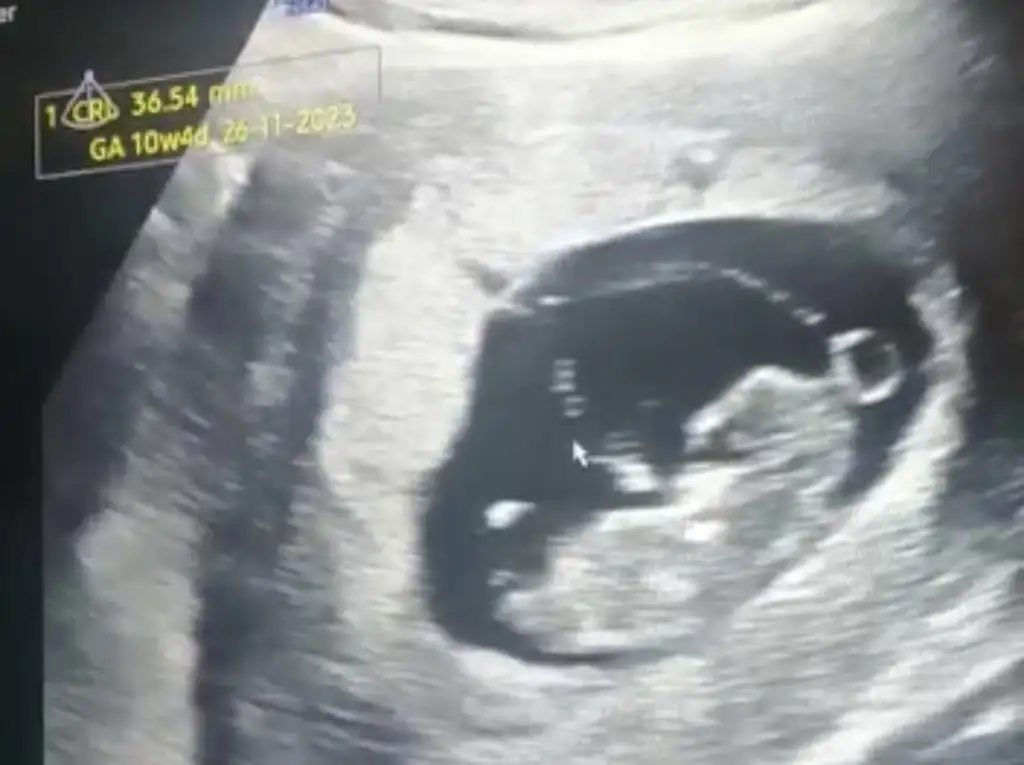

12+6 dedi